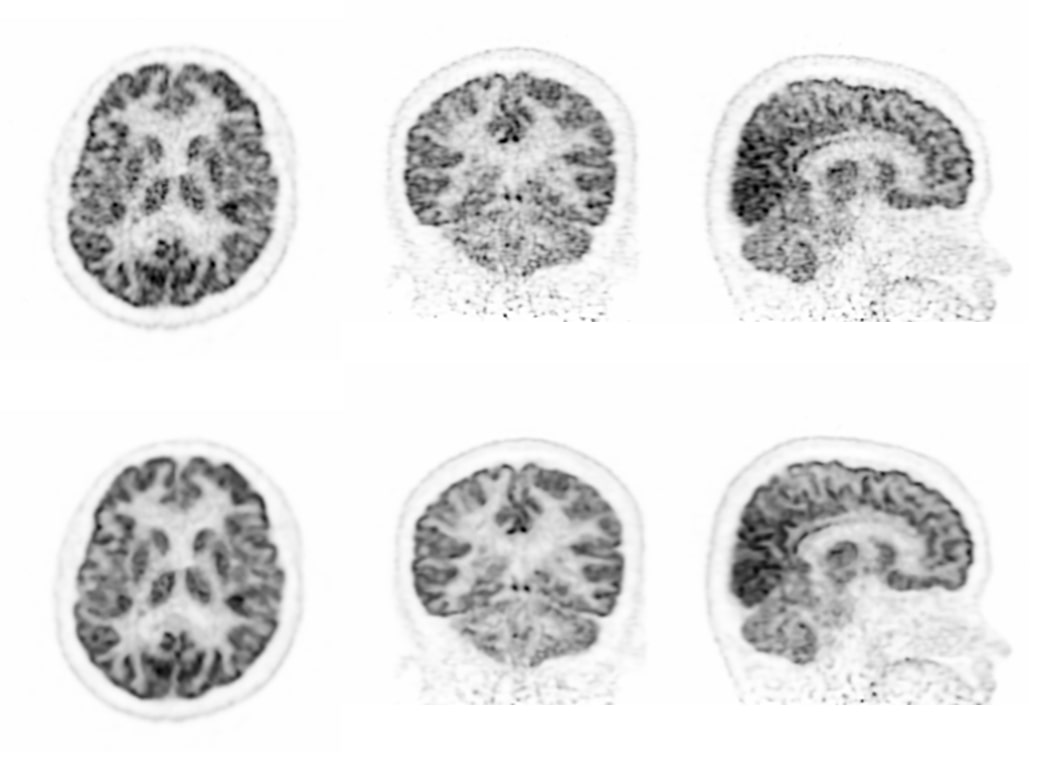

全采样重建

低计数图像重建

超低计数68Ga三符合重建

缺角度数据图像重建

采用单事件、低能量事件等全流程数据进行全数字PET图像重建,解决低剂量、多核素等场景下高质量成像问题。

传统算法 改进的算法 双符合重建68Ga和18F混合的信号 三符合重建仅含68Ga的信号 传统算法 改进的算法 缺角度系统